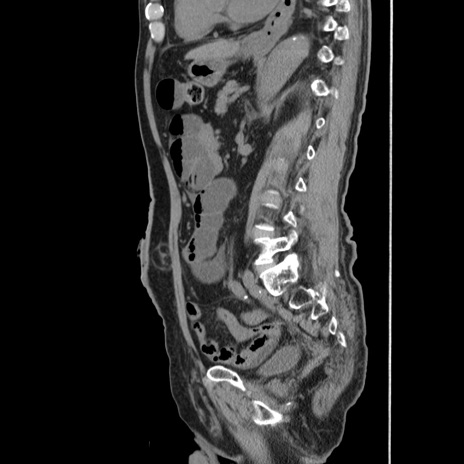

症例24(矢状断像)

【症例】80歳代男性

【主訴】左側腹部痛、嘔吐

【現病歴】本日早朝より左腹部に痛みあり。昼頃嘔吐認めたため、救急要請。

【既往歴】直腸癌(Mile手術)、胆摘

【身体所見】意識清明、BT 35.9℃、BP 221/93mmHg、SpO2 97%(RA) 、腹部:左ストーマ周囲に限局性の腹部膨隆あり。 膨隆部自発痛・圧痛あり・軟。

【データ】WBC 7700、CRP 0.09